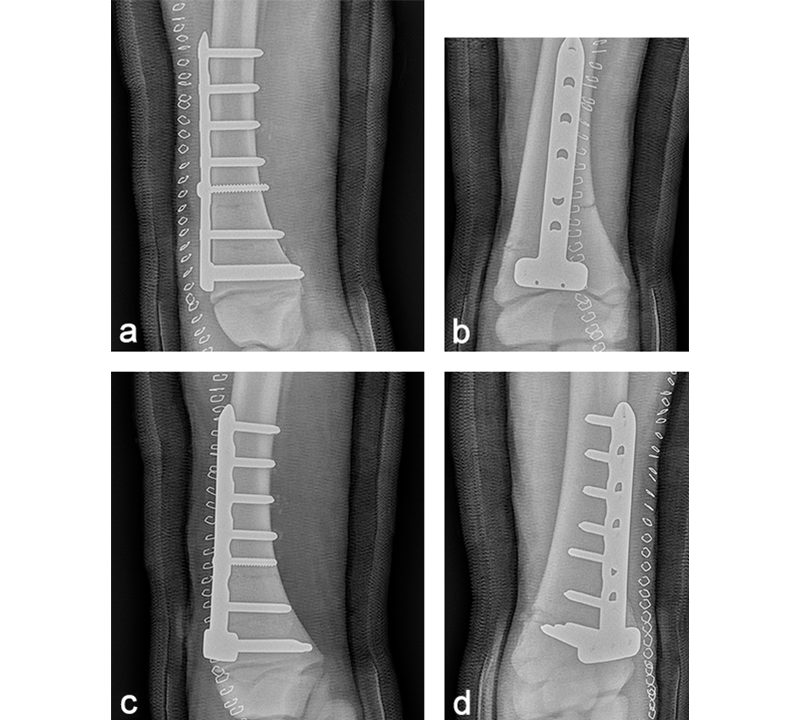

The day after admission, the mare was placed under general anesthesia in dorsal recumbency for a partial carpal arthrodesis of the right carpometacarpal and middle carpal joints. The middle carpal joint was examined arthroscopically, and all visible articular cartilage was removed by using a combination of manual (bone curette) and motorized (shaver/burr) instrumentation (Fig 6). A 4.5 mm drill bit was used to drill across the carpometacarpal joint surfaces. A cancellous bone graft harvested from the sternum was loosely packed into the repair through an arthroscopic portal with the leg in flexion. Following graft insertion, implants were placed using a minimally invasive technique, tunneling the plate under the skin and joint capsule, and stab incisions for screw insertions. A 6-hole LCP Equine T-plate 4.5 was applied to the dorsal aspect of the limb deep to the extensor tendons and joint capsule through an enlarged arthroscopic portal between the extensor carpi radialis and common digital extensor tendon using a plate passer. A 4.5 mm cortex screw was placed in the first hole of the shaft of the plate to compress the plate to the bone. Two 5.0 mm locking screws were placed in the holes of the horizontal portion of the plate to engage the intermediate carpal bone. A third 5.0 mm locking screw was placed into the radial carpal bone using the last hole of the horizontal portion of the plate (Fig 7). All remaining holes were filled with 5.0 mm locking screws except the second hole, which was left empty because the hole was directly over the carpometacarpal joint. A 6-hole narrow LCP 4.5 was applied dorsolaterally and a 6-hole narrow LCP 4.5 was placed dorsomedially in a similar manner. The skin incisions were closed in routine fashion, and a sterile dressing and full limb cast were applied. The mare recovered uneventfully from anesthesia with head and tail assistance.

The cast was removed 24 hours postoperatively, and a Robert- Jones bandage with caudal and lateral splints was maintained for 1 month. The mare made excellent postoperative progress with immediate full weightbearing on the operated leg. At 5 months postoperatively, radiographic evaluation confirmed excellent healing of the fracture and almost complete fusion of the middle carpal and carpometacarpal joints with preservation of the radiocarpal joint (Fig 8). At one year postoperatively, the mare showed a very good cosmetic aspect of the carpus, as well as an excellent locomotion at three gates, with only minor mechanical lameness due to reduction of carpal flexion (Fig 9).